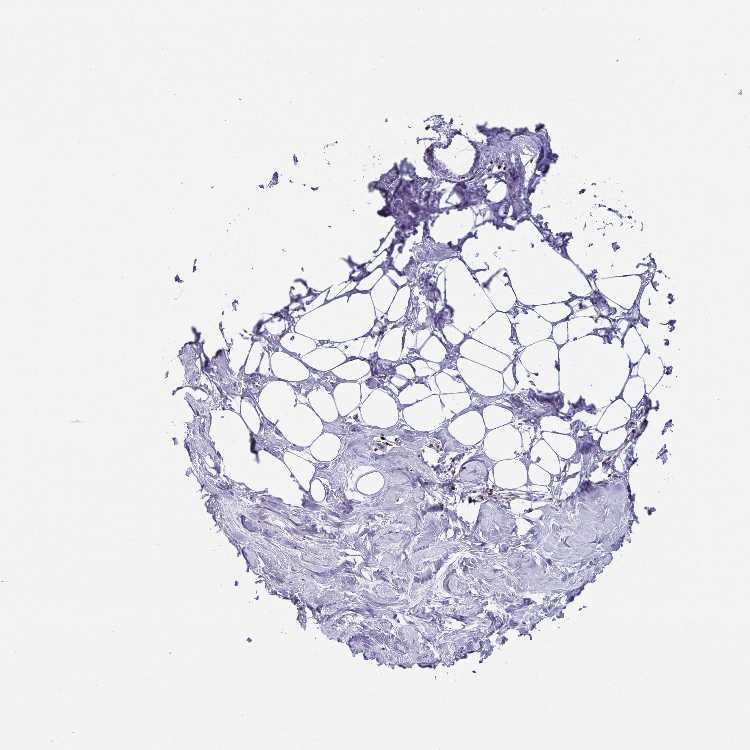

TISSUE PRIMARY DATA BREAST Show tissue menu

Breast

BREAST - Expression summary

BREAST - Antibody stainingi

Antibody staining in the annotated cell types in the current human tissue is reported as not detected, low, medium, or high, based on conventional immunohistochemistry profiling in selected tissues. This score is based on the combination of the staining intensity and fraction of stained cells.

Each image is clickable and will lead to virtual microscopy that enables deeper exploration of all samples and also displays staining intensity scores, fraction scores and subcellular localization as well as patient and tissue information for each sample.

Antibody HPA060782

Adipocytes Not detected

Glandular cells Not detected

Myoepithelial cells Not detected